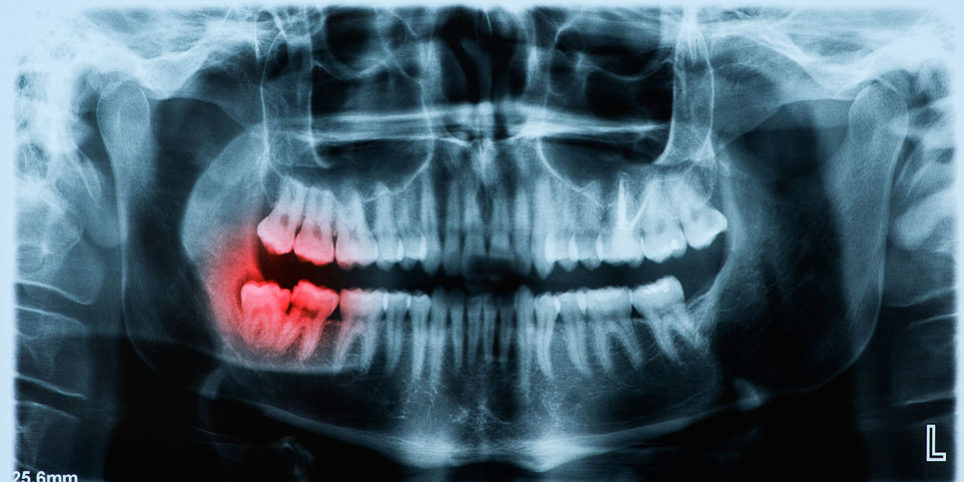

Periodontal disease is similar to other chronic diseases, such as diabetes. The key to control is early diagnosis and prompt treatment. Often times, one may not even experience pain until the disease is in its advanced stages.

More than half of people aged 55 and older have periodontitis. Risk factors that may make older people more susceptible include general health status (i.e diabetes), diminished immune status, medications, depression, osteoporosis, stress, smoking, worsening memory, diminished salivary flow, and change in financial status.